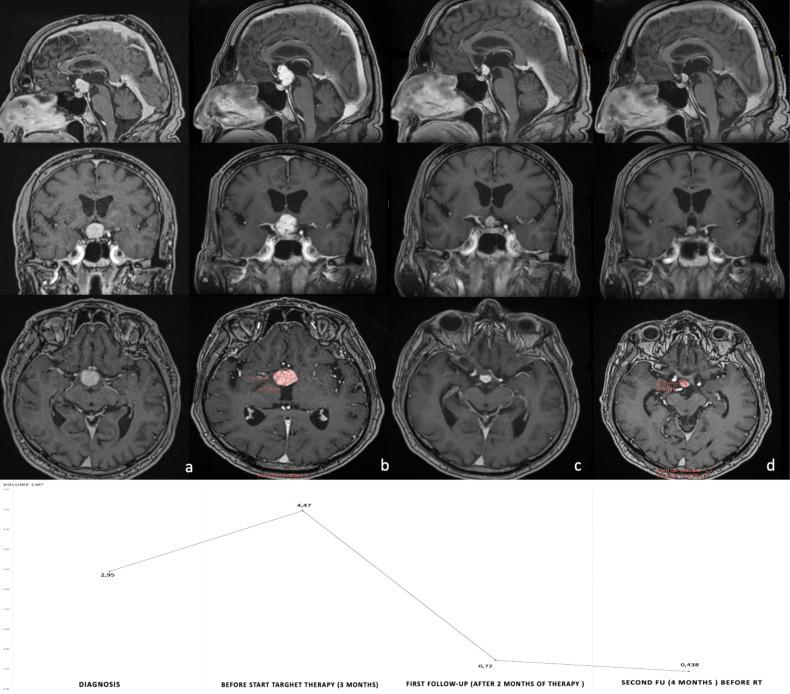

We report herein two cases of tubero-infundibular and ventricular Papillary Craniopharyngiomas in which BRAF/MEK inhibitor combined therapy was used as adjuvant (Case 1) or neoadjuvant (Case 2) treatment, with a 90% reduction in tumor volume observed after only 5 months. In Case 2 the only surgical procedure used was a minimal invasive biopsy by the trans-ventricular neuroendoscopic approach. As a consequence, targeted therapy was administered in purely neoadjuvant fashion. After shrinkage of the tumor, both patients underwent fractionated radiotherapy on the small tumor remnant to achieve long-term tumor control. A review of a previously reported case has also been performed.

我们在此报告两例鞍上-漏斗和脑室的乳头状颅咽管瘤,其中 BRAF/MEK 抑制剂联合治疗作为辅助(病例 1)或新辅助(病例 2)治疗,仅在 5 个月后观察到肿瘤体积减少 90%。在病例 2 中,唯一使用的手术方法是通过经脑室神经内镜进行微创活检。因此,靶向治疗以纯粹的新辅助方式进行。肿瘤缩小后,两名患者均接受分割放疗以控制残余肿瘤,实现长期肿瘤控制。还对以前报告的一例病例进行了回顾。